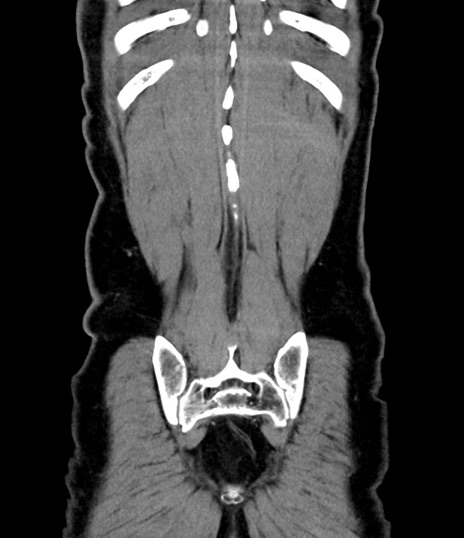

症例8(冠状断像)

【症例】 60歳代男性

【主訴】 黒色吐物

【現病歴】 4日前から嘔気自覚、2日前の朝食後にも嘔気あり、自分で手で嘔吐反射起こし嘔吐したところ血が混ざっていたため受診。

【既往歴】 5年前汎発性腹膜炎を伴う急性虫垂炎で手術、高血圧、前立腺肥大症、高脂血症

【身体所見】 腹部正中に手術癩痕あり 腹部平坦・軟圧痛なし膨満感あり

【データ】WBC 8400、CRP 4.54